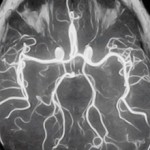

У человека, так же как и у млекопитающих, постоянная температура тела, которая не зависит от окружающей среды. Это постоянство является результатом сложных механизмов терморегуляции, обеспечивающих обменные процессы. Контролирует их центральная нервная система и центр головного мозга - гипоталамус. Он принимает сигналы от нервных окончаний и посылает к разным системам нашего организма. Теплообмен осуществляется за счет теплоотдачи и теплопродукции.

У грудничков теплопродукция происходит за счет процессов окисления в бурой жировой ткани. Она есть только у плода и у новорожденного ребенка. Бурый жир вырабатывается с двадцать шестой недели беременности и к моменту рождения ребенка составляет до 8 % от массы его тела. Она находится в области шеи, за грудиной, между лопаток. Особенностью этого механизма является то, что под воздействием работы щитовидной железы максимальное тепло вырабатывается при минимальных энергетических затратах. Вторым важным механизмом в процессе теплоотдачи является мышечное дрожание. Если понижается температура тела, то непроизвольные сокращения мышц повышают ее. Если кроха замерз, он начинает плакать и активно двигаться. Это приводит к повышению температуры тела.

Теплоотдача - это процессы потоотделения и тонуса кровеносных сосудов. У взрослого человека при повышении температуры начинается активное потоотделение. У грудничка потовые железы еще не развиты, поэтому малыш не сильно потеет. Также при повышении температуры у новорожденного расширяются сосуды кожи, и усиливается теплоотдача. И в обратном порядке, когда при понижении температуры тонус кровеносных сосудов повышается и уменьшается теплоотдача. У взрослого хорошо развита подкожная жировая клетчатка. У грудничка же ее практически нет, поэтому, когда сужаются кожные сосуды, продолжается потеря тепла. Особенностью малыша является склонность к перегревам из-за неразвитости потовых желез, и к переохлаждениям из-за отсутствия жирового слоя.